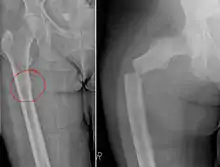

Chalkstick fracture due to bone metastasis of breast cancer. Left image shows the metastasis, on the right a pathological fracture a few days later.

Chalkstick fractures are fractures, typically of long bones, in which the fracture is transverse to the long axis of the bone, like a broken stick of chalk.[1] A healthy long bone typically breaks like a hard woody stick as the collagen in the matrix adds remarkable flexibility to the mineral and the energy can run up and down the growth rings of bone. The bones of children will even follow a greenstick fracture pattern.

Chalkstick fractures are particularly common in Paget's disease of bone, and osteopetrosis.[2] It is also seen in cases of fused spine as in a patient with ankylosing spondylitis.[3]